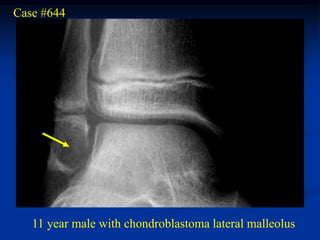

Case #644

11 year male with chondroblastoma lateral malleolus

Sagittal T-1 MRI

Axial T-2 MRI

Photomic